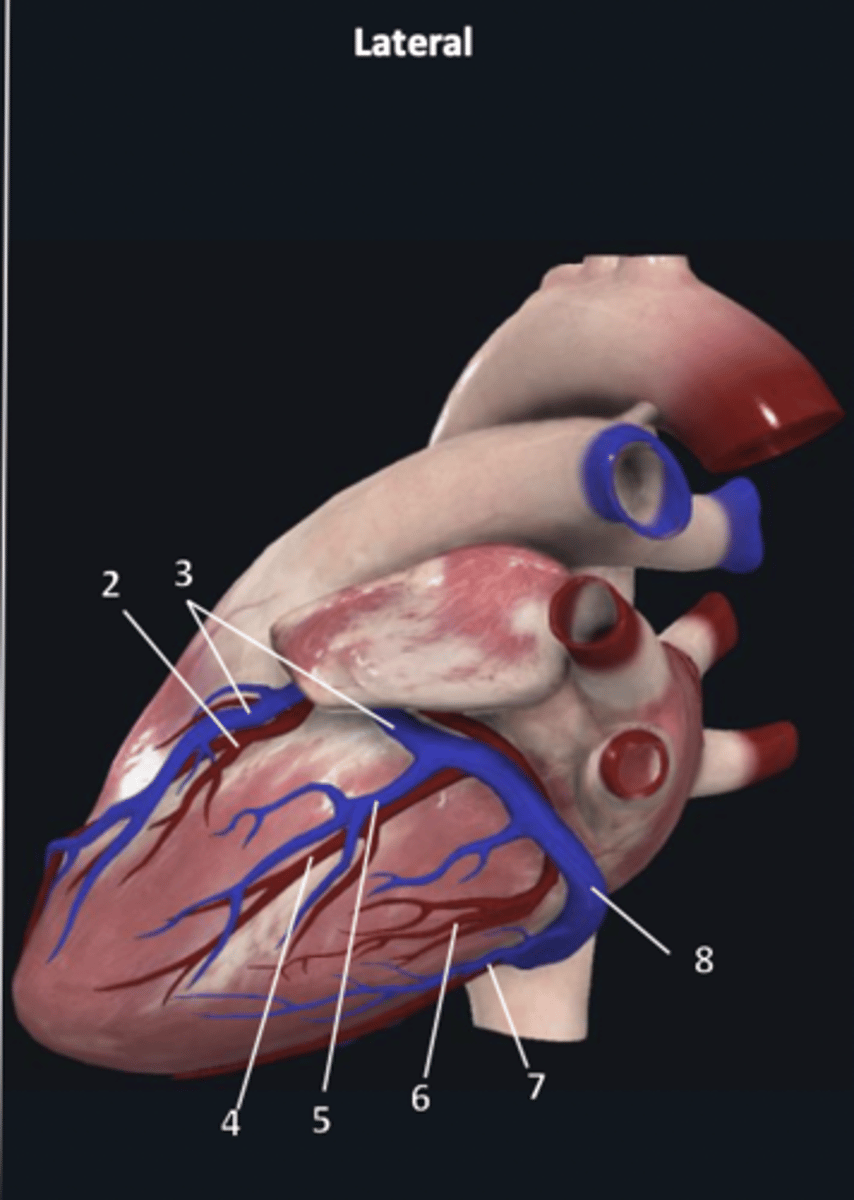

right coronary artery

1

anterior interventricular artery

2 (red)

great cardiac vein

3 (blue)

anterior interventricular artery

2 (red)

great cardiac vein

3 (blue)

left marginal artery

4

left marginal vein

5

posterior left ventricular artery

6

posterior vein of left ventricle

7

coronary sinus

8